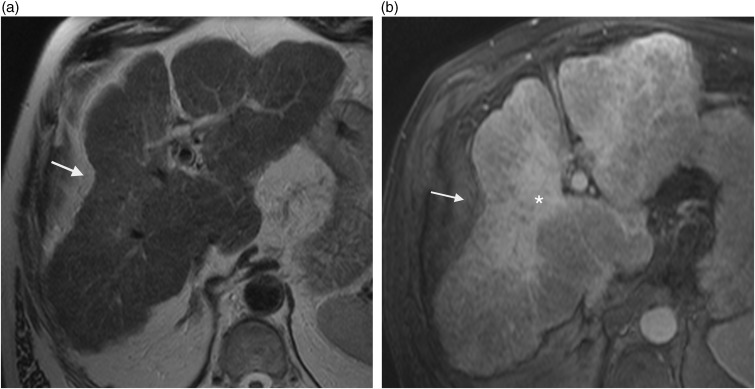

Hepatic capsular retraction is an imaging feature that deserves the attention of the radiologist. Hepatic capsular retraction is associated with a number of hepatic lesions, benign or malignant, treated or untreated. The purpose of this pictorial review is to discuss the most common benign and malignant hepatic lesions associated with this feature with an emphasis on magnetic resonance imaging (MRI).